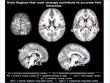

A new, very early version of a “painometer” is being tested at Stanford. The tests are actually sort of medieval-sounding, but to test pain, you’ve got to inflict pain. Subjects were touched with a heat probe (on the arm, people) and the ensuing brain signals were measured. Those measurements were used to create an algorithm that, the researchers hoped, would be able to indicate pain.

The algorithm does work, though not perfectly; the current accuracy rating is around 81%, which is plenty to show that it works but also not nearly high enough to actually rely on.